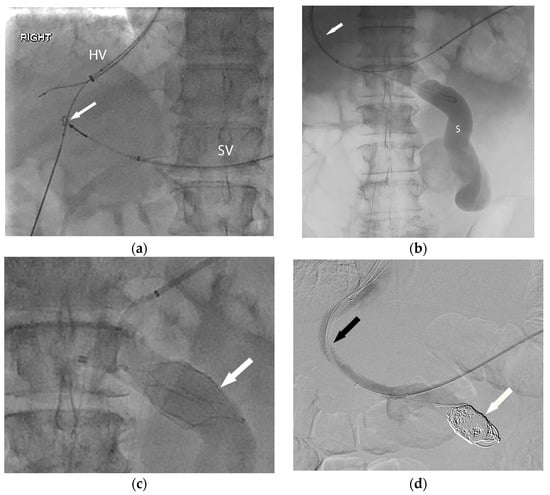

PVR-TIPS techniques: The ability to successfully perform a PVR-TIPS requires mastery of several core building-block techniques that are generally employed in step-wise fashion (Figure 2). First, the steps of a standard TIPS placement procedure should be performed, including obtaining right internal jugular vein access, placement of a 10 Fr sheath, obtaining a baseline right atrial pressure measurement, and catheterization of the right hepatic vein [42,43,44]. Once in position, the cannula device from a TIPS kit is then placed within the sheath, and in cases of partially or minimally occlusive thrombosis, access into the portal vein is obtained utilizing standard techniques. In complete or chronic occlusion (with or without cavernous transformation), transhepatic or transplenic techniques are utilized to obtain access into the thrombosed portal system.

Figure 2.

In order to facilitate listing for liver transplantation, the patient (Figure 1) was referred for portal vein recanalization and transjugular intrahepatic portosystemic shunt (TIPS) placement. (a) This required both hepatic vein (HV) and splenic vein (SV) access, and a “gun-sight” technique (arrow) was used to reconstruct the portal vein. (b) With the TIPS deployed (arrow), the large shunt (S) was next addressed. (c) An inferior vena cava filter (arrow) was used in an off-label manner to form a scaffold for coil embolization of the large portosystemic shunt. Final angiography (d) demonstrates a patent TIPS (black arrow) and occluded portosystemic shunt (white arrow).

Initial series described transhepatic access to gain access into the thrombosed portal system; however, more recent series described a higher technical success rate for the procedure with the use of transplenic access into the portal system [43], which has been the experience at our center. In cases where transplenic access is unfavorable or unable to be employed, transmesenteric access has also been utilized as a possible method for portal vein recanalization [46]. In the case of transplenic access, a 21 G needle is advanced under ultrasound guidance into an intraparenchymal splenic vein branch and a 0.018 inch nitinol wire is advanced through the needle into the splenic vein. At this point, an Accustick sheath (Boston Scientific Corporation, Marlborough, MA, USA) is placed into the splenic vein and a long digital subtraction image of the portal venous system is obtained and portal pressures are obtained. Oftentimes, a faint diminutive caliber thrombosed portal vein can be identified coursing superiorly towards the liver hilum, and at this point utilizing an angled catheter and glide wire the portal vein is recanalized and a small amount of contrast is injected to confirm intrahepatic portal vasculature. Even in cases with extensive chronic thrombosis with cavernous transformation, a long DSA run will often opacify the obliterated portal vein or identify the coronary vein, which can be used as a landmark to identify the chronically thrombosed segment. Once access is confirmed, the main portal vein is dilated with an 8 mm high-pressure balloon to restore patency and facilitate TIPS access and placement. After balloon dilation, TIPS is performed via the standard technique via the right internal jugular access, and in the event of difficult access into the portal system, a snare is placed via the transplenic access in order to help target the access site and obtain through and through access. After obtaining portal access and measuring the tract length, stent deployment is carried out in a fashion so as to maximize the amount of unstented portal vein in order to facilitate end-to-end anastomosis during surgery (Figure 3). Additional considerations during stent placement include ensuring that the superior portion of the stent is not extended into the inferior vena cava or right atrium or that the inferior portion of the stent does not extend into the retropancreatic region. Additionally, it is worth noting that stent placement is highly center- and surgeon-dependent so these discussions should take place prior to the procedure. After stent deployment, the entirety of the stent and parenchymal tract is dilated with a 10 mm high pressure balloon and in the event of recalcitrant stenosis or thrombosis, a 12 mm high pressure balloon. Post-TIPS DSA images are obtained and in the event of large collateral vessels influencing portal vein and TIPS flow, these are embolized at the time of the procedure to maximize portal vein flow. At the conclusion of the procedure, post-TIPS creation main portal and right atrial pressures are obtained. The splenic access site may be closed utilizing gelfoam pledgets, although prior operators have reported the use of coils with high technical success [44].